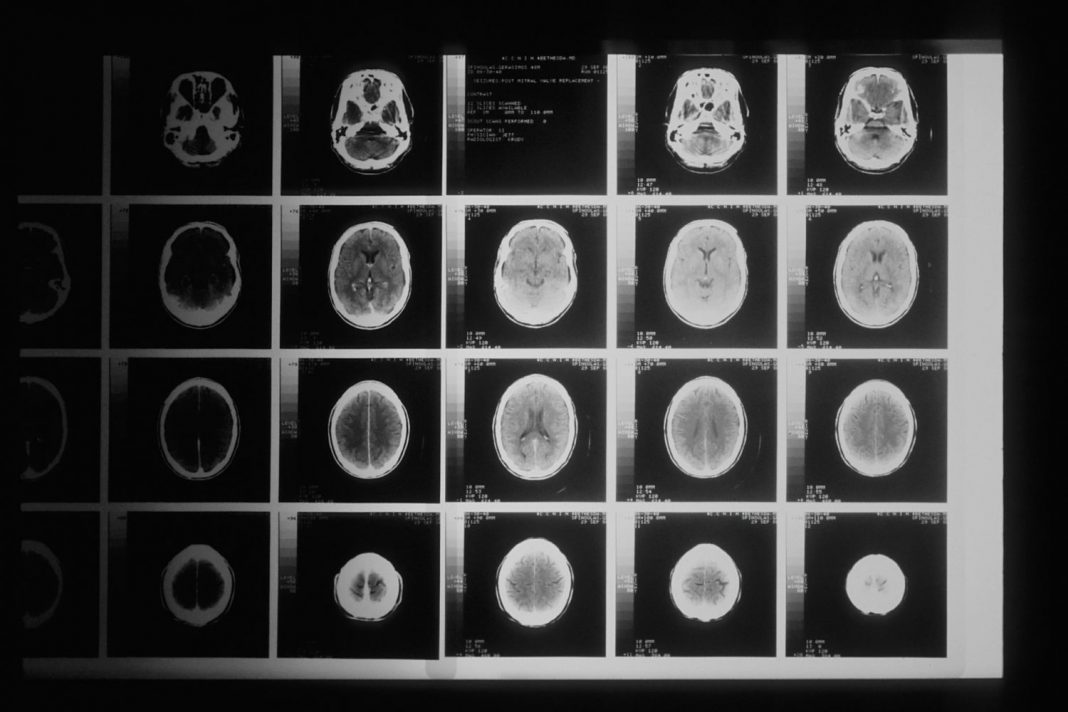

8 Ictus isquémico

Se denomina isquémico cuando el ictus es producto de una obstrucción de los vasos sanguíneos, esto se debe a la acumulación de grasa en las paredes de los vasos sanguíneos, estos trombos son conocidos como trombos cerebrales o embolismo.

- Ataque isquémico transitorio: Es un episodio de corta duración de déficit neurológico, se estima entre hora y media a dos horas de evolución. Usualmente, estos pacientes vuelven a sufrir un ictus isquémico.

- Ictus isquémico total: Es cuando se afecta una arteria cerebral media que provoca la disfunción cerebral superior, déficit motor.